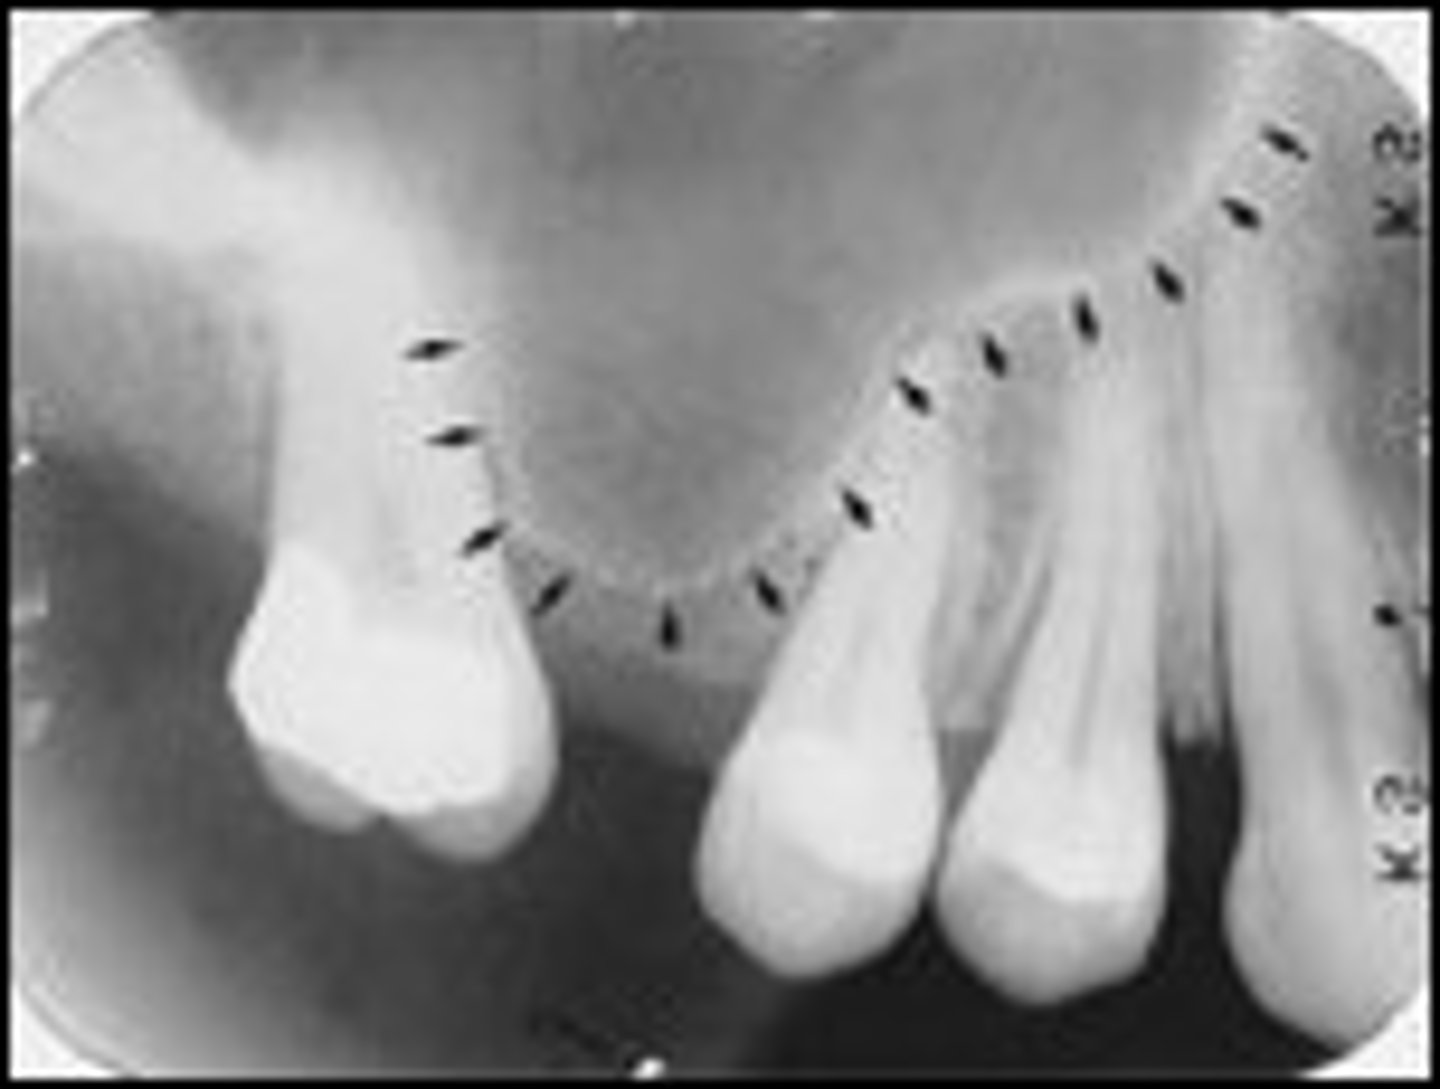

Nutrient canals within the maxillary sinus

What is the radiolucent structure seen here?